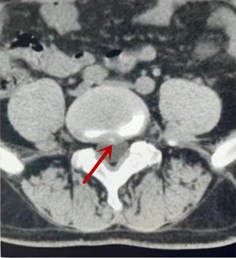

利器二:CT

CT利用X射線對人體檢查部位通過電腦切成若干層掃描,然后把每層的圖像都能顯示出來。CT相對于X光片具有更高的密度分辨力,可直接顯示X線片無法顯示的病變,觀察腰椎有無微小的骨折、骨質(zhì)有無破壞等骨質(zhì)情況、以及腰椎間盤突出、腰椎神經(jīng)根、椎管、椎間小關(guān)節(jié)的情況等。同時還可以通過后處理,重建腰椎矢狀位或冠狀位圖像,形成腰椎的3D圖像,更直觀地觀察病變部位,對腰椎手術(shù)風(fēng)險具有提示作用,對手術(shù)方式的選擇具有指導(dǎo)意義,但是對神經(jīng)、脊髓損傷程度的顯示不如MRI,軟組織的分辨率仍有一定限制,對椎管內(nèi)病變顯示欠佳,且有一定的輻射。

箭頭提示椎間盤突出